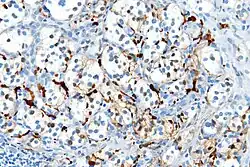

On microscopic inspection, the tumor cells are readily recognized. Individual tumor cells are polygonal to oval and are arranged in distinctive cell balls, called Zellballen.[9] These cell balls are separated by fibrovascular stroma and surrounded by sustentacular cells.

With immunohistochemistry, the chief cells located in the cell balls are positive for chromogranin, synaptophysin, neuron specific enolase, serotonin, neurofilament and Neural cell adhesion molecule; they are S-100 protein negative. The sustentacular cells are S-100 positive and focally positive for glial fibrillary acidic protein. By histochemistry, the paraganglioma cells are argyrophilic, periodic acid Schiff negative, mucicarmine negative, and argentaffin negative.

Micrograph of a carotid body tumor -

S100 immunostain highlighting the sustentacular cells in a paraganglioma -